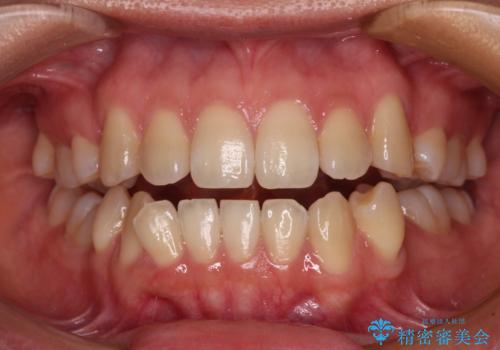

[ マウスピース矯正治療 ] がたつき ねじれのある前歯をきれいにしたい

![[ マウスピース矯正治療 ] がたつき ねじれのある前歯をきれいにしたいの症例 治療前](https://seimitsushinbi.jp/wp/wp-content/uploads/2025/04/8438e7299f1b9566ac213e8e9f7db5f6-500x350.jpg?v=1745226068)